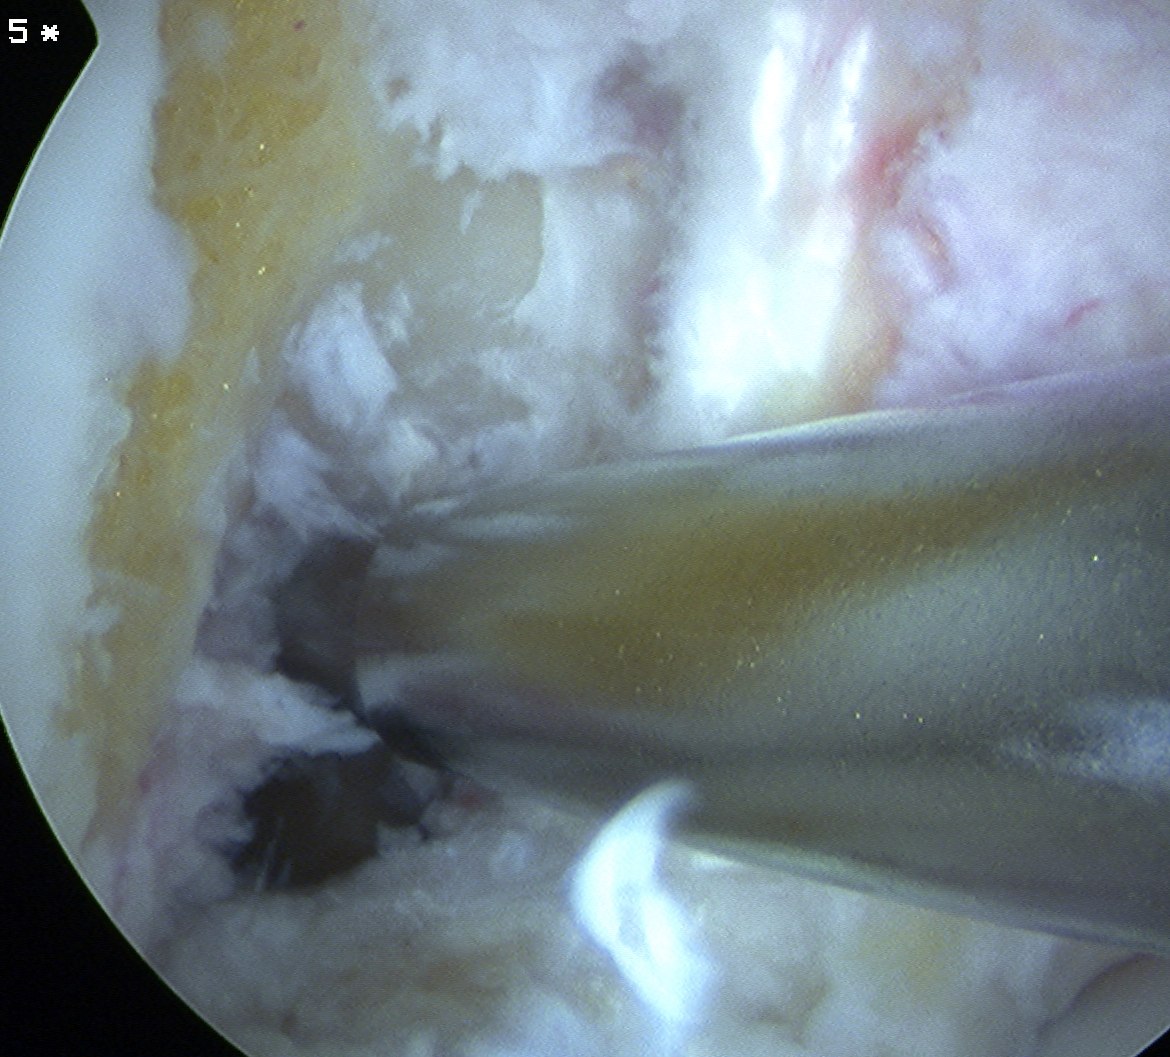

Assess and manage mensicus as appropriate

- assess and manage chondral lesions as appropriate

Debride ACL

Debride stump back to PCL fibres (preserve synovium over PCL)

- can leave some stump to identify tibial tunnel and provide vascularisation

- clean lateral wall

- remove periosteum with curette, chondrotome and electrocautery

- identify resident's ridge and posterior wall clearly